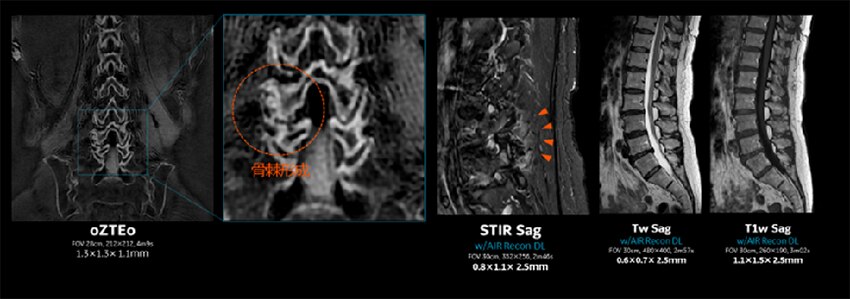

Figure. 4

oZTEoにより、一回のMRで炎症性変化と、骨棘形成を同時に観察することが出来る。

MRIで軟部組織の診断と併せて骨情報を得ることが出来ることで、患者さんの一連の検査のワークフローが改善される。Fig. 4は、腰椎のルーチン検査に、oZTEoを追加撮像した症例である。STIRで浮腫が見られる領域に、oZTEoで骨棘が形成されており、浮腫と伴う急性期の変化と、骨棘形成を伴う慢性的な変化の部位に浮腫を伴う急性期の変化が同時に起こっていることが確認されている。これは良く起こりえる病態ではあるが、腰痛の検査の際にMRIとCTをside by sideで読影をすることはほぼなく、oZTEoにより今まで気に留めていなかった病態の変化に新ためて確認することができる。